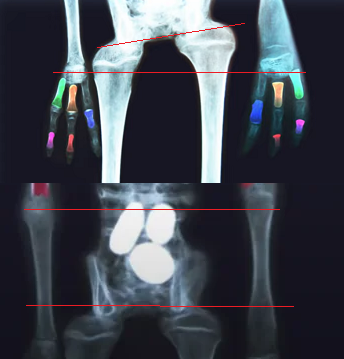

The problem: This screenshot from this video by Scientists Against Myths [7:48] is Josefina's x-ray, the hi-res photos of which can be downloaded from the Antropogenez link above. It shows some bones in each hand are upside-down on opposite sides of the body. While we could argue an alien might evolve upside-down phalanges compared to us, they would not plausibly be asymmetrical.

1696151420688.png

The problem: This screenshot from this video by Scientists Against Myths [7:48] is Josefina's x-ray, the hi-res photos of which can be downloaded from the Antropogenez link above. It shows some bones in each hand are upside-down on opposite sides of the body. While we could argue an alien might evolve upside-down phalanges compared to us, they would not plausibly be asymmetrical

Sure, one bone is vice versa.

mummy.png

...or five. Not sure about what is going on out in the distal ends of the fingers, which sort of fade out in this image, but I make out roughly 6-7 un-reversed bones, 5 reversed. That's reasonably close to what you might expect by random chance, just inserting bones blindly with no thought or knowledge of which way they should go. The only thing seemingly missing is a case where chance led the same bone to be reversed in each hand. Perhaps that shows up in another of the "mummies?"

Also, while I'm not a professional anatomist or anything, those long bones in the leg both appear upside down, if they are even the correct bones.

It's not just the upside-down phalanges. What passes for the knees and hand/wrist are made up from different bones and are asymmetrical. There is no apparent pelvis, at least not one with the appropriate sockets for the ball of the femur, nor is there any ball on whatever is passing for the femur, to rotate in resulting in a working hip joint. This thing literally can't walk:

1697900783870.png

Actual human hip joint:

1697900863294.png